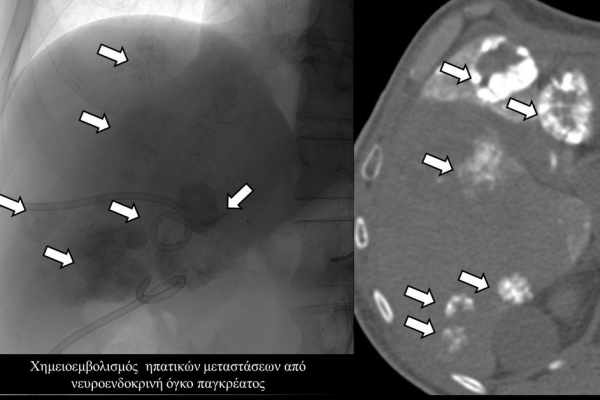

Ενδείκνυται επίσης σε ηπατικές μεταστάσεις από νευροενδοκρινείς όγκους, καρκίνο παχέος εντέρου και μελάνωμα, σε συνδυασμό με συστηματική χημειοθεραπεία της οποίας ενισχύει και βελτιώνει τα αποτελέσματα.